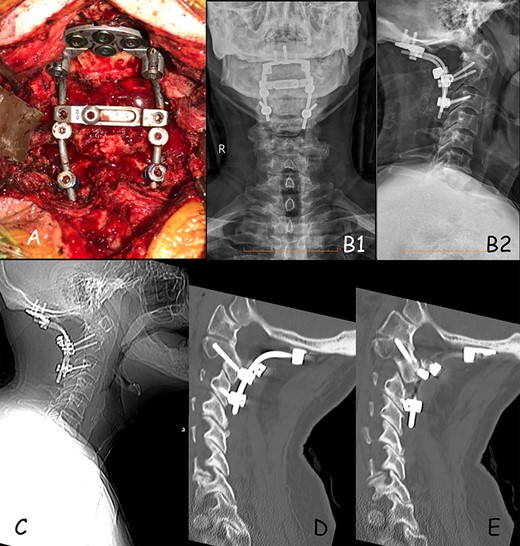

The patient was prescribed a cervical orthosis (Miami J collar) for 3 months post-operatively. Day 1 post-operative CT demonstrated satisfactory hardware positioning. Follow up X-ray at 4 weeks and CT at 12 months demonstrated good implant positioning without evidence of migration (Fig. 3). Neck pain and upper limb symptoms were significantly improved, and patient has been functioning well.

(A) Intra-operative positioning of occipital plate and screws construct. (B) 1-month post-op X-ray, (B1) anterior–posterior and (B2) lateral X-ray. (C) 12-months post-op lateral X-ray showing good positioning of construct. (D) Sagittal CT demonstrating good positioning of construct on the right side. (E) Sagittal CT demonstrating good positioning of construct on the left side.